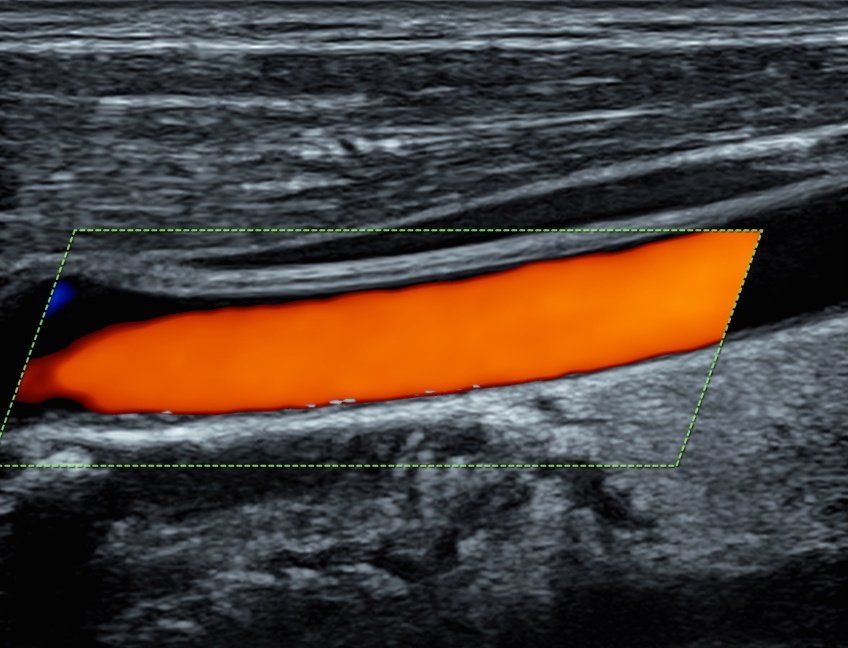

La diagnostica Eco-Color-Doppler si rende utile sia nello studio degli organi interni sia nella valutazione dei distretti vascolari arteriosi e venosi. Gli esami eco-color-Doppler sono indicati per lo studio delle carotidi/tronchi sovra-aortici (patologie cerebro-vascolari e cardiologiche), per la valutazione dell’aorta addominale (aneurismi, dissecazioni), per la valutazione delle arterie degli arti inferiori (arteriopatia ostruttiva, diabete), per la valutazione delle vene degli arti inferiori (insufficienza venosa, varici arti inferiori).